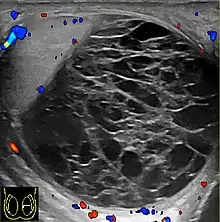

Hemoscrotum can follow trauma (such as a straddle injury) or can be a complication of surgery. It is often accompanied by testicular pain. It has been reported in patients with hemophilia and following catheterization of the femoral artery. If the diagnosis is not clinically evident, transillumination (with a penlight against the scrotum) will show a non-translucent fluid inside the scrotum. Ultrasound imaging may also be useful in confirming the diagnosis. In severe or non-resolving cases, surgical incision and drainage may be required. To prevent recurrence following surgical drainage, a drain may be left at the surgical site.

- Ultrasound

Current research is ongoing for proper diagnosis and helping to differentiate among other conditions. Doppler ultrasound in a retrospective study was shown to be helpful for differential diagnosis of patients with acute scrotum.[13] Accuracy of imaging studies is higher for the differential diagnosis of testicular torsion and epididmo-orchitis, which there can still be the possibility of misdiagnosis for hematoceles due to testicular torsion.[13] Further research in this area shows importance for surgical decision making in hematoceles.[13]